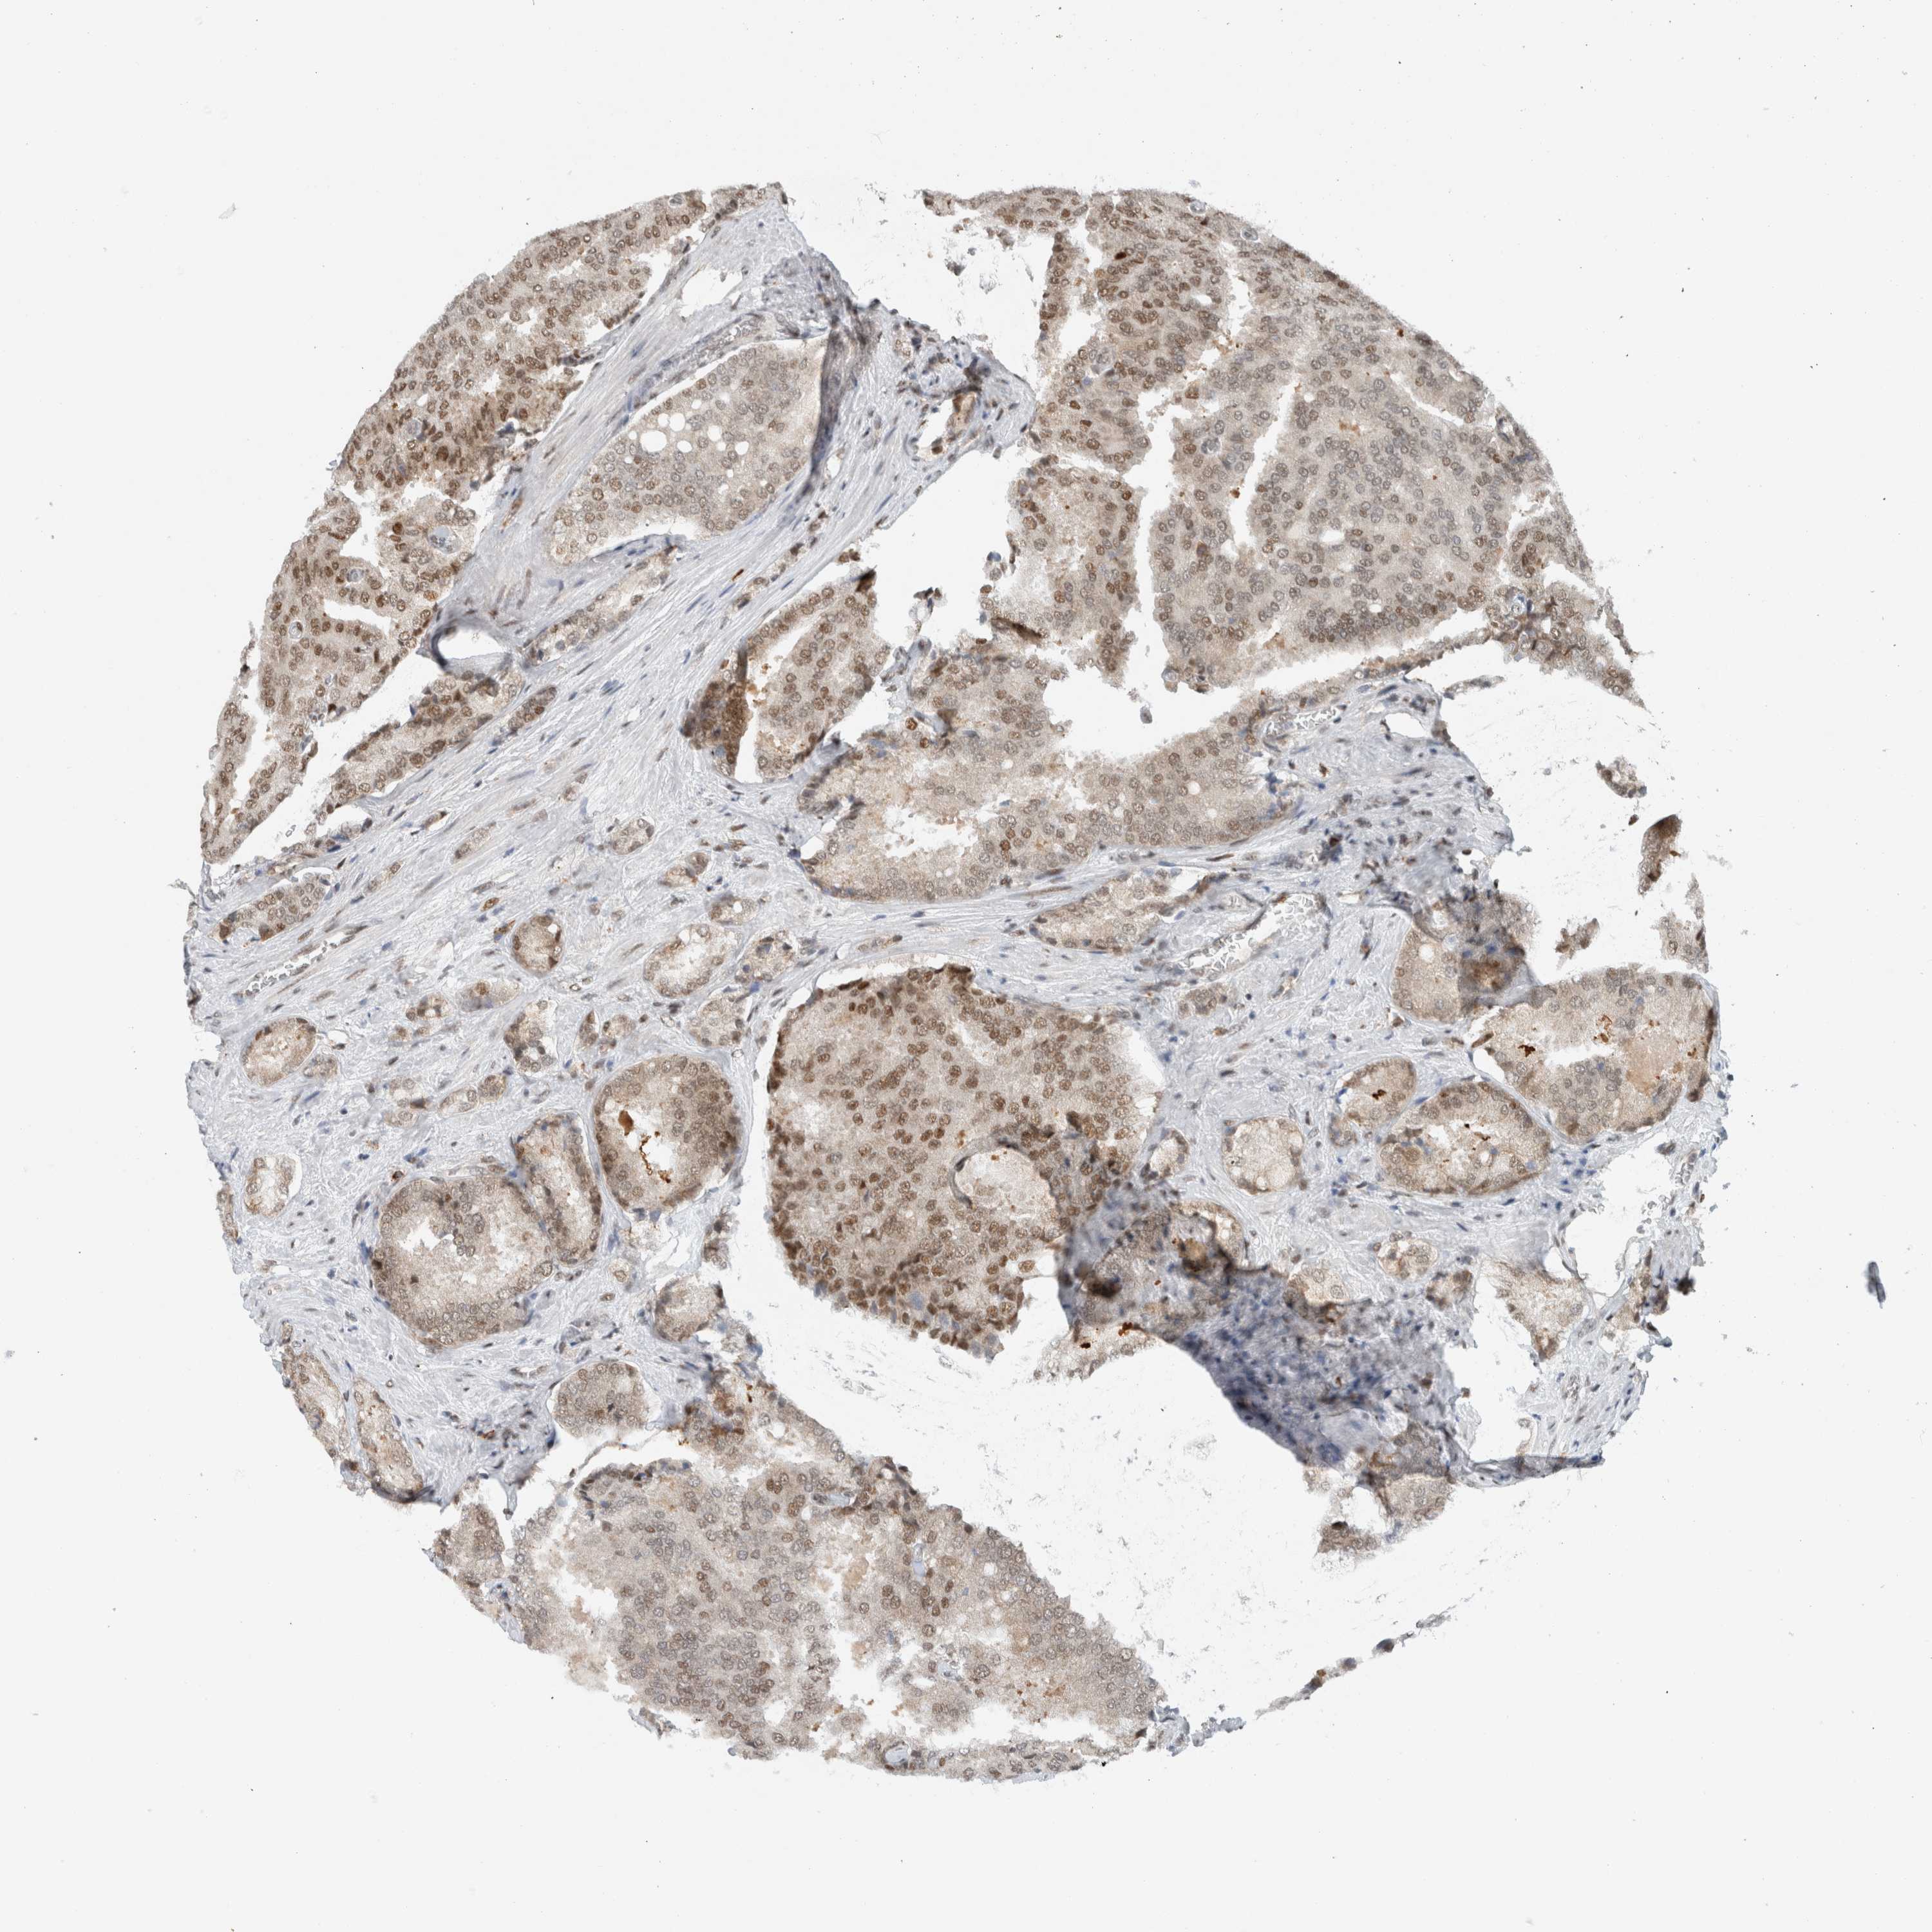

PROSTATE CANCER - Protein expressioni

A mouse-over function shows sample information and annotation data. Click on an image to view it in a full screen mode. Samples can be filtered based on level of antibody staining by selecting one or several of the following categories: high, medium, low and not detected. The assay and annotation is described here.

Antibody stainingi

Antibody staining in the annotated cell types in the current human tissue is reported as not detected, low, medium, or high, based on conventional immunohistochemistry profiling in selected tissues. This score is based on the combination of the staining intensity and fraction of stained cells.

Each image is clickable and will lead to virtual microscopy that enables deeper exploration of all samples and also displays staining intensity scores, fraction scores and subcellular localization as well as patient and tissue information for each sample.

Antibody CAB011687

Staining

High

Medium

Low

Not detected

Intensity

Strong

Moderate

Weak

Negative

Quantity

>75%

75%-25%

<25%

None

Location

Nuclear

Cytoplasmic/membranous

Cytoplasmic/membranous,nuclear

Adenocarcinoma, High grade

Adenocarcinoma, Low grade